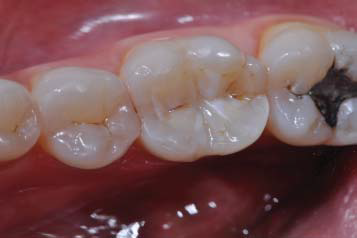

After checking occlusion with articulating paper and setting with a fine-grained diamond bur, the occlusal contacts were adjusted using a polishing cup (Figure 4). After the end of the restorative procedures, the patient was instructed about what foods to avoid in the first 24 hours and was asked to return for evaluation. In the first two weeks, the patient reported a reduction in pain, but it did not disappear. A month later, pain was mild and only felt when the patient had cold or hot foods. At that time, the patient was examined, and occlusion was once again evaluated and adjusted, and the restoration underwent finishing and polishing. Monitoring after that revealed a reduction of symptoms. After seven years, the patient reported no pain. The clinical examination revealed that the restoration remained satisfactory and there were no stains or infiltrations signs (Figura 5) The monitoring radiograph ruled out periodontal lesions or periapical pathologies (Figure 6).